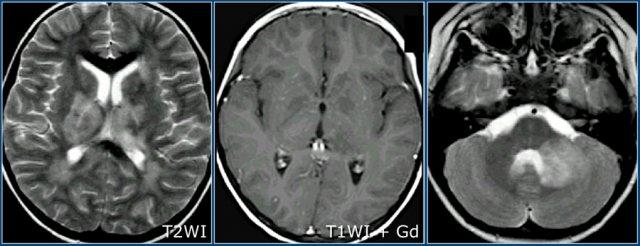

MS dạng u (Tumefactive MS)

MS dạng u là một thể biến thể của bệnh xơ cứng rải rác.

Trên MRI, bệnh biểu hiện là một tổn thương lớn trong nhu mô não với hiệu ứng khối thường ít hơn so với kích thước của nó.

Các tổn thương này có thể biểu hiện ngấm thuốc ngoại vi, thường với dạng vòng nhẫn hở (incomplete ring), khác với u thần kinh đệm (glioma) hoặc áp xe trong nhu mô não, vốn thường có dạng ngấm thuốc vòng nhẫn kín.

Đây là các hình ảnh chuỗi xung T2W và T1W sau tiêm thuốc tương phản từ của một nam bệnh nhân 39 tuổi nhập viện với bán manh khởi phát bán cấp.

Bệnh nhân được chỉ định sinh thiết để phân biệt giữa u thần kinh đệm và bệnh mất myelin.

Có một khối trong nhu mô não ở thùy thái dương và thùy chẩm phải với viền giảm tín hiệu trên T2, chỉ ngấm thuốc một phần (dấu hiệu vòng nhẫn hở) trên các hình ảnh sau tiêm thuốc tương phản từ.

Có phù nề xung quanh nhưng hiệu ứng khối tương đối ít.

Đây là tổn thương mất myelin được xác nhận qua sinh thiết.

Dạng ngấm thuốc vòng nhẫn hở kết hợp với viền giảm tín hiệu T2 và lưu lượng máu não (CBF) thấp đều là các dấu hiệu gợi ý bệnh mất myelin.